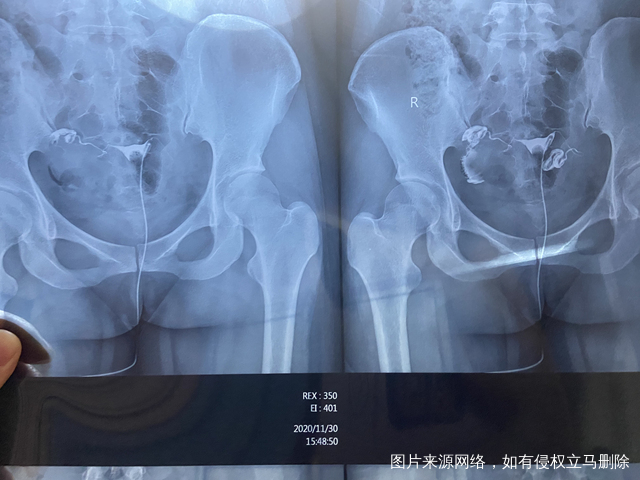

想请教下从片子上看粘连的情况严重么是两边都有